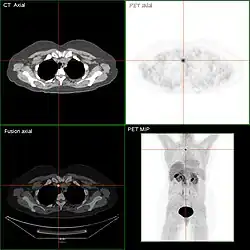

- In der Schilddrüsenszintigraphie sind kalte Knoten in 3 % der Fälle ein Karzinom (einzelner kalter Knoten: 15 %), sonst Entzündungen, Fibrosen, Verkalkungen, Zysten, Blutungen oder Adenome.

Nach sechs bis zwölf Monaten (frühestens nach drei Monaten) sollte in bestimmten Fällen das Ergebnis der Radiojodtherapie mit einer sogenannten Radiojoddiagnostik dokumentiert werden.[18][19] Im Hormonentzug (vier Wochen vor der Untersuchung keine Einnahme des L-Thyroxins) wird eine geringe Menge Jod-131 verabreicht und die Verteilung im Körper nach 48 Stunden mit einer Szintigraphie ermittelt. Auch für diese Radiojoddiagnostik ist – hier bereits seit 2001 – ein Hormonentzug nicht mehr notwendig (s. o.). Bei dem Einsatz von rhTSH zur Vorbereitung einer Radiojoddiagnostik muss allerdings bedacht werden, dass für eine eventuell notwendige erneute Radiojodtherapie auch das rhTSH erneut verabreicht werden muss.